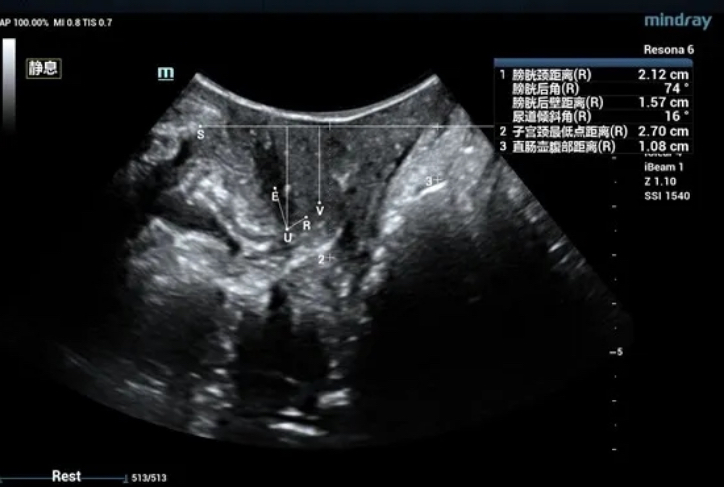

The bladder neck is located 21.2mm above the pubic symphysis at rest, the uterus is located 27.0mm above, and the rectum is located 10.8mm above (see Figure 1).

Figure 1 Two-dimensional ultrasonic measurement of pelvic floor structural parameters at rest